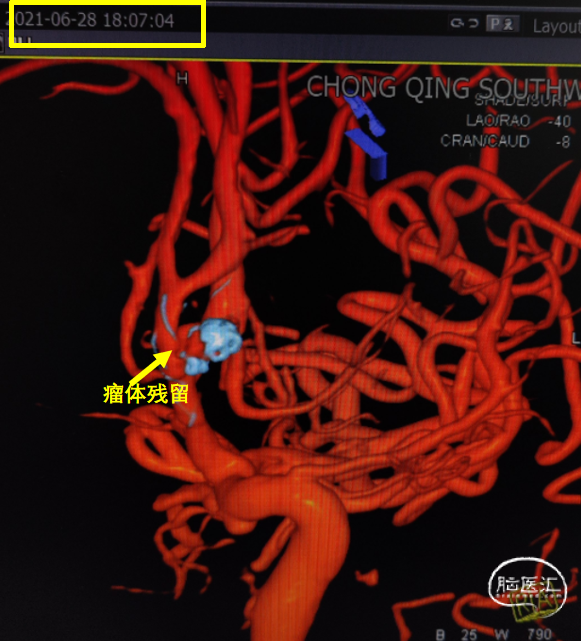

造影见对侧大脑前血流恢复,远端瘤体已致密栓塞,但近端瘤体存在残留;

双融积成像显示支架打开贴壁良好,瘤体少量残留。